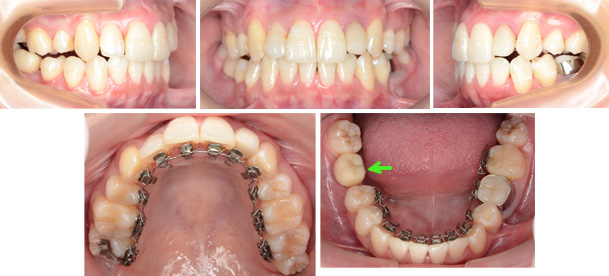

治療中の写真

ある程度矯正治療が進んだ状態を示します。緑色の矢印に示す歯のはインプラントの仮の歯です。2歯抜歯されているのでインプラントを治療前にインプラント専門医に埋入してもらいました。インプラントは1本です。大臼歯がこの状態では満足のいく矯正治療はできません。そこで治療に入る前に患者様には説明し、ご納得頂いてインプラントを埋入してもらい仮の歯を装着してもらいました。下顎前歯にも叢生があるのでこの排列に必要なスペースを想定してインプラントは少し後方に設置してもらいました。ブラケットが外れた後に仮の歯を交換します。